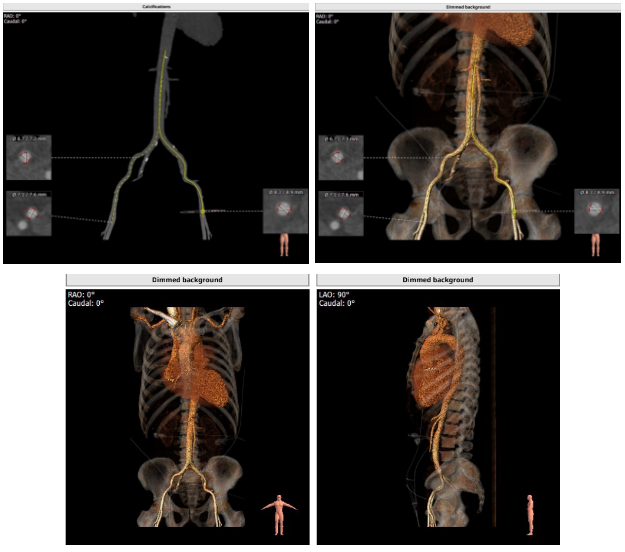

解剖结构

主动脉根部解剖动态图:

主动脉根部解剖:

血管入路解剖: